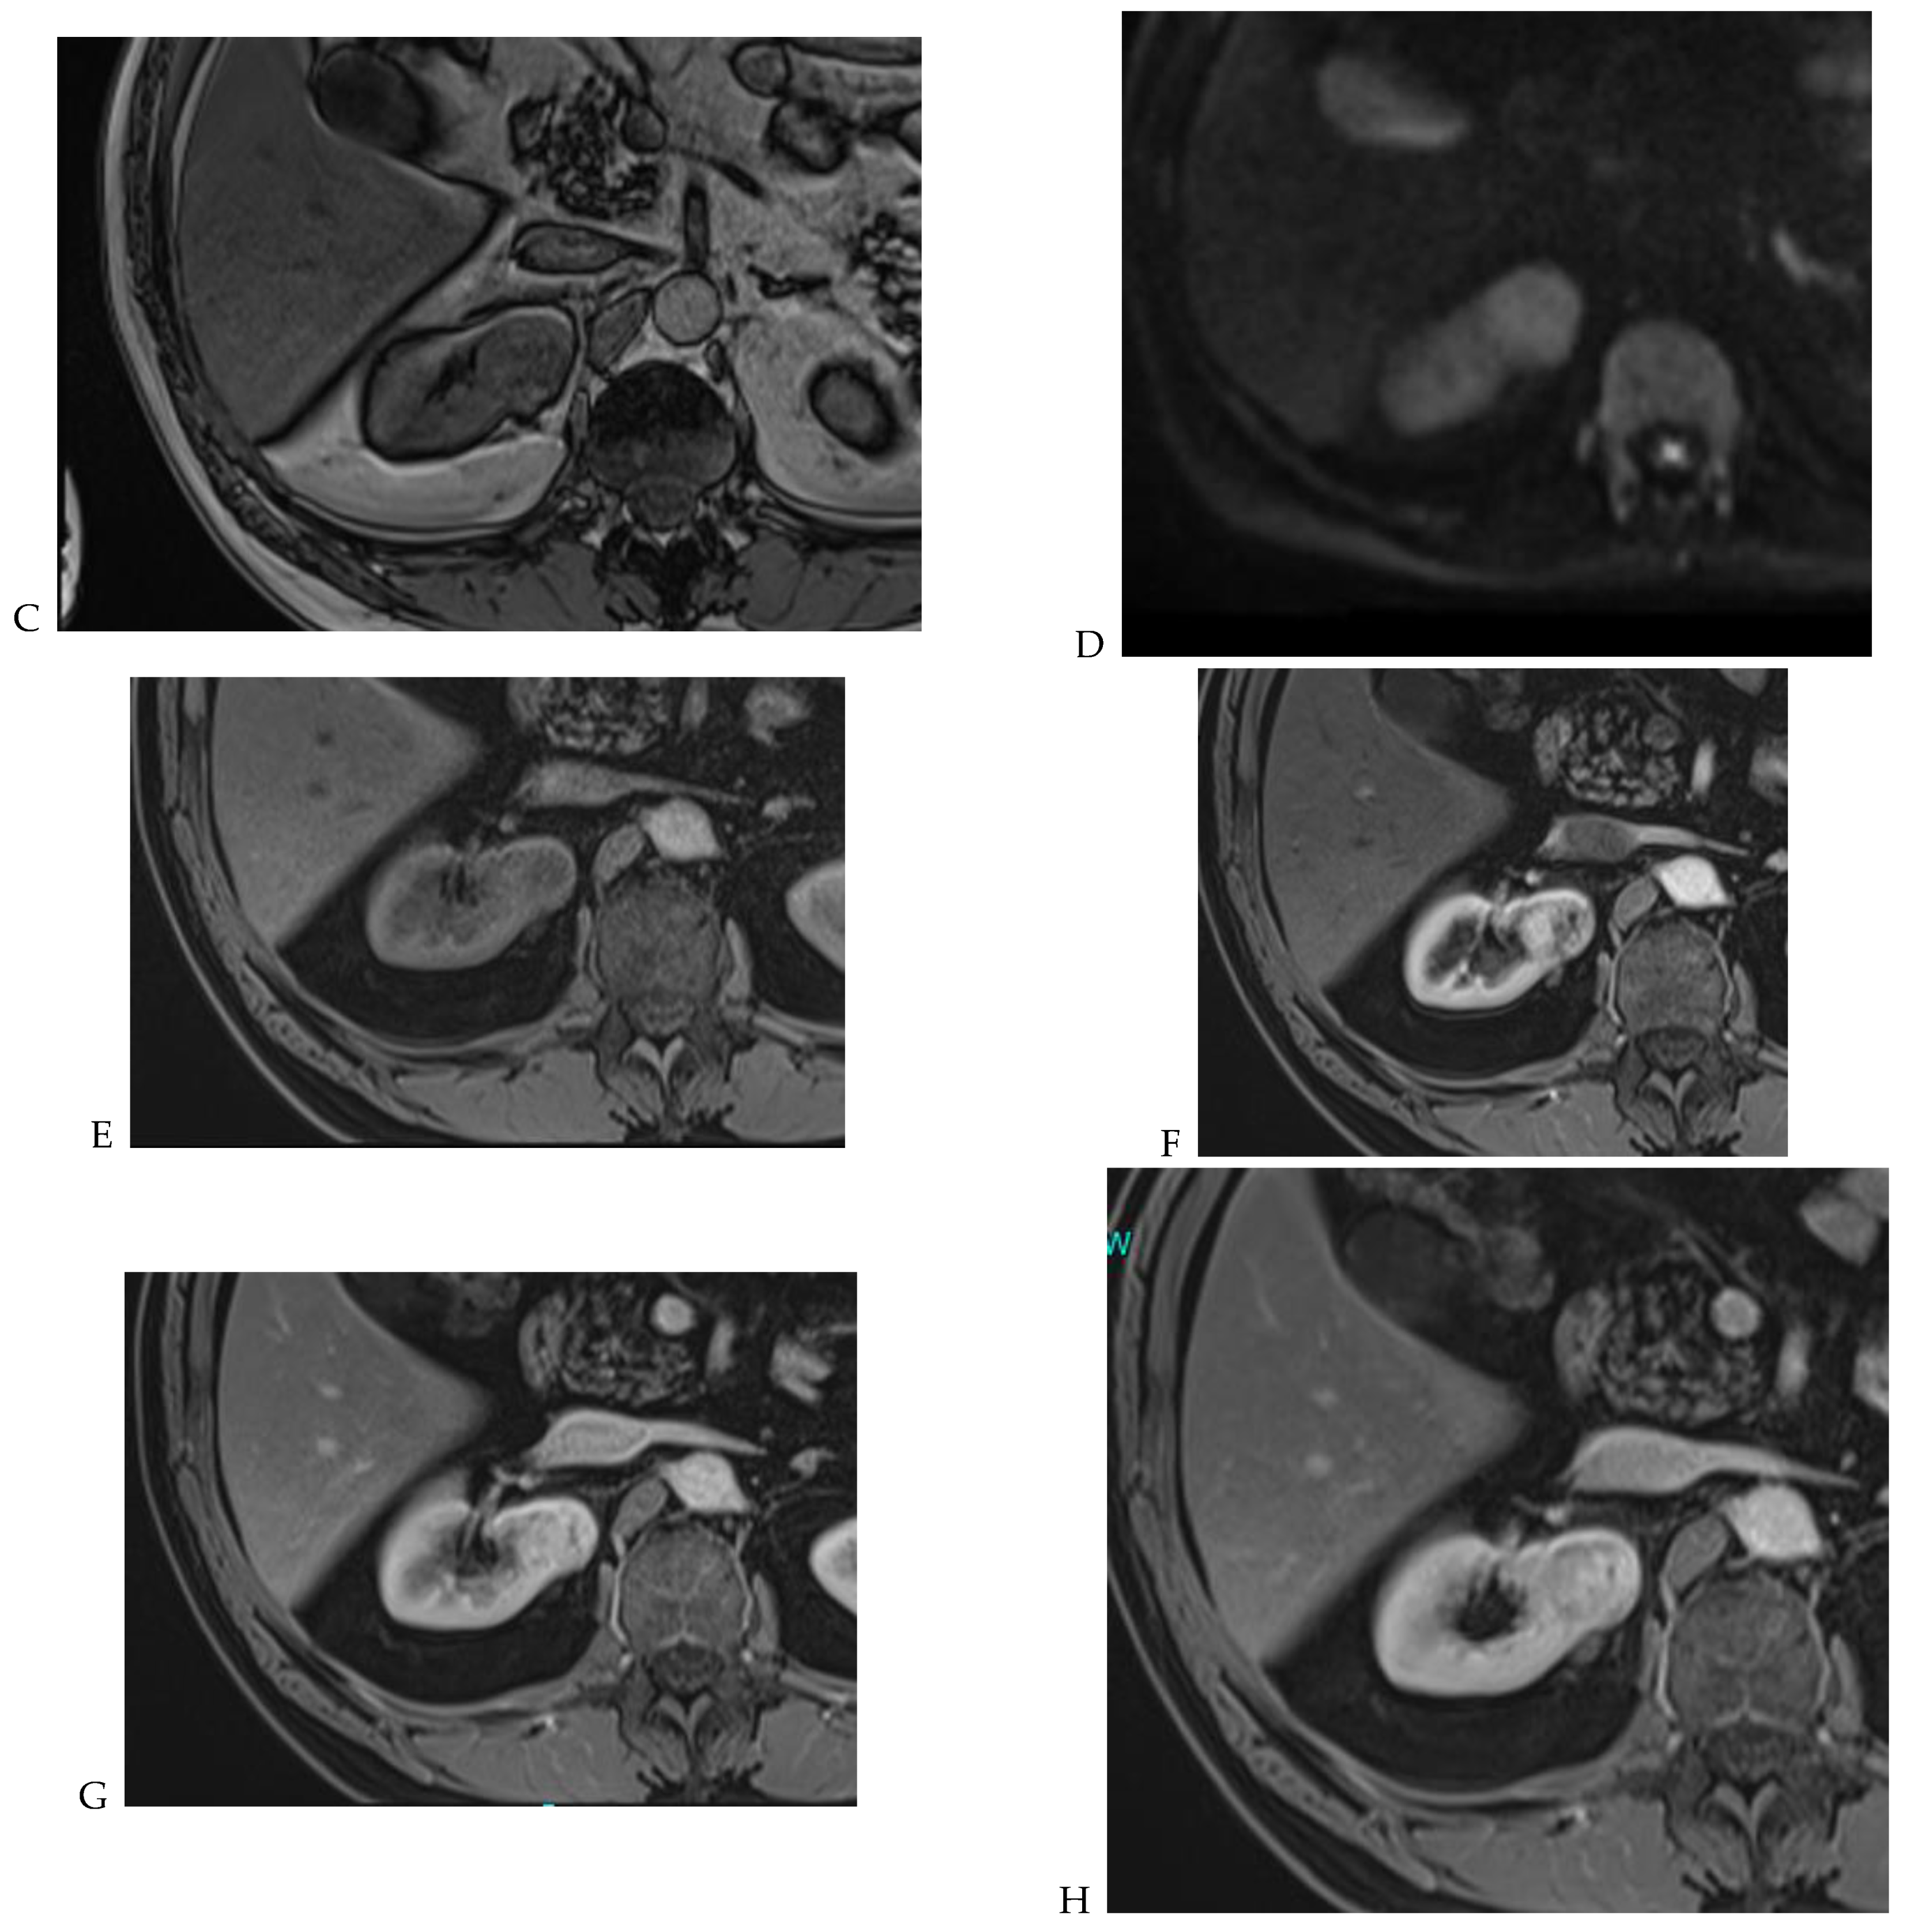

Figure 7.

Papillary renal cell carcinoma in the right kidney of a 75-year-old-woman. (A) Axial T2-weighted fast SE image shows a homogeneous 1.8 cm mass in the posterolateral region of the right kidney, with a lower SI compared to renal parenchyma. Transverse in-phase (B,C) opposed-phase MR images do not show a significant signal loss on the opposed-phase image. (D) The ADC map shows restriction of tumor diffusion into the renal mass. Transverse nonenhanced (E) and gadolinium-enhanced T1-weighted gradient-echo spoiled MR images in (F) corticomedullary, (G) nephrographic, (H) and delayed phase images show progressive enhancement without washout; the mass is hypovascular compared to the renal cortex.